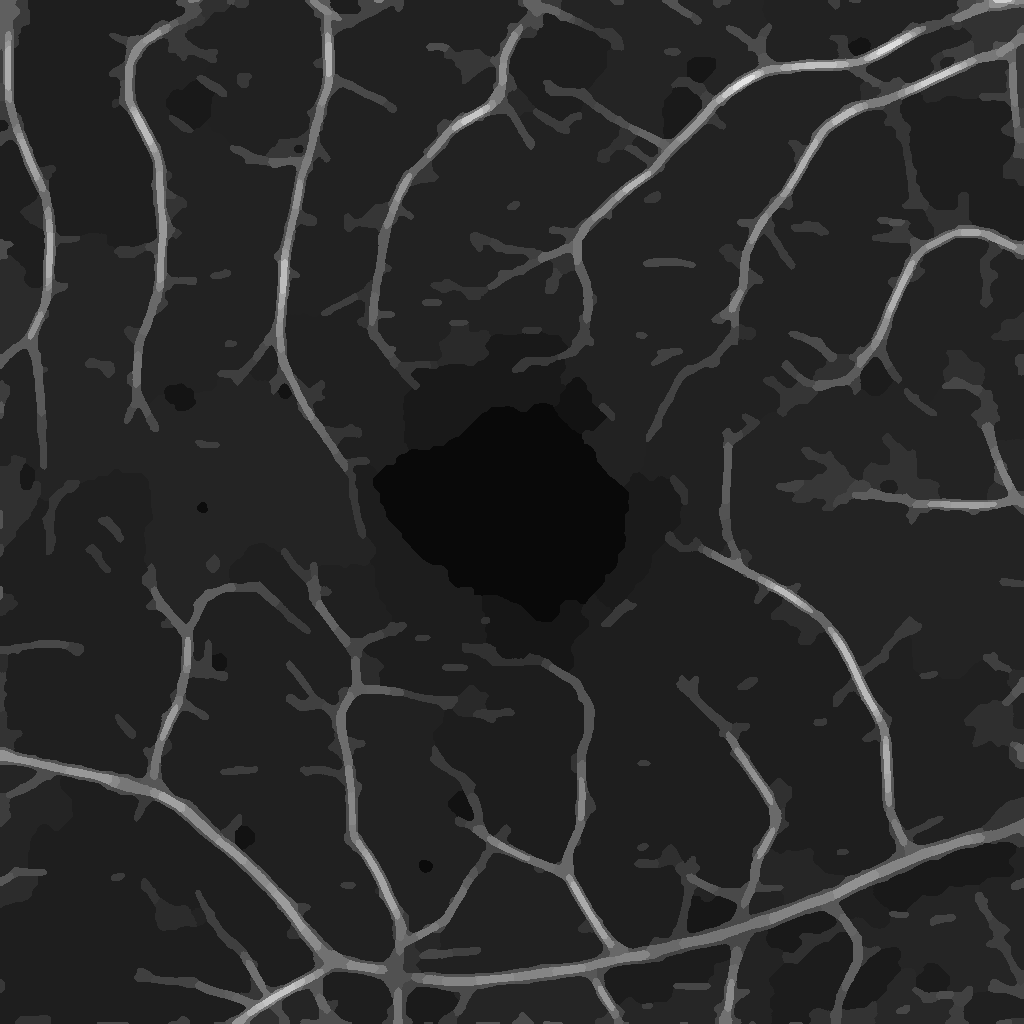

for some chosen frequency ω𝜔\omega, orientation θ𝜃\theta and σ1subscript𝜎1\sigma_{1}, σ2subscript𝜎2\sigma_{2} correspond to the spatial widths of the filter, which is then applied to an image. Here, we choose the parameters as suggested in [19] and use 333 frequency scalings {ωi}i=13superscriptsubscriptsubscript𝜔𝑖𝑖13\{\omega_{i}\}_{i=1}^{3} and 666 orientations {θj}j=16superscriptsubscriptsubscript𝜃𝑗𝑗16\{\theta_{j}\}_{j=1}^{6} to create our Gabor filter bank. The 36=1836183\cdot 6=18 computed Gabor filters are then convolved with the original image Im×n𝐼superscript𝑚𝑛I\in\mathbb{R}^{m\times n} to derive the new image representations in m×nsuperscript𝑚𝑛\mathbb{R}^{m\times n}. Next, for fixed ωisubscript𝜔𝑖\omega_{i}, we take the pixel-wise maximum in the images corresponding to the 666 orientations {θj}j=16superscriptsubscriptsubscript𝜃𝑗𝑗16\{\theta_{j}\}_{j=1}^{6}, leading to 333 images I1,I2,I3subscript𝐼1subscript𝐼2subscript𝐼3I_{1},I_{2},I_{3} with different emphasized frequency ranges, see Figure 1. These new representations are our basis for the further processing.

Refer to caption

(a) I1subscript𝐼1I_{1}: High frequencies

(b) I2subscript𝐼2I_{2}: Medium frequencies

(c) I3subscript𝐼3I_{3}: Low frequencies

Figure 1: New image representations are obtained by the convolution of the original image I𝐼I with Gabor filters. The images I1,I2,I3subscript𝐼1subscript𝐼2subscript𝐼3I_{1},I_{2},I_{3} correspond to the 333 chosen frequency ranges defined by {ωi}i=13superscriptsubscriptsubscript𝜔𝑖𝑖13\{\omega_{i}\}_{i=1}^{3}.

(a) Original image

(b) Final segmentation

Figure 2: The combined substeps described in Sections 2.1 and 2.2 yield the final image.